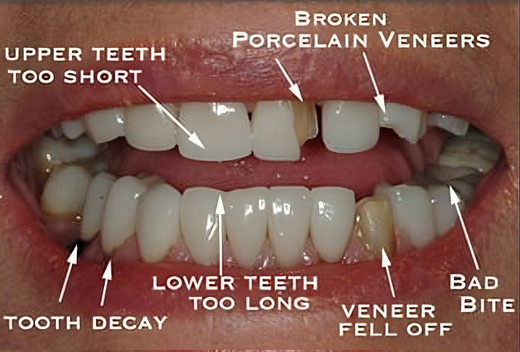

Full Mouth Rehabilitation

Full mouth rehabilitation also known as full mouth reconstruction involves restoring or rebuilding teeth in both upper and lower jaws simultaneously.

This may involve one or more of the following procedures like crowns, bridges, implants, filings, extractions, gum reshaping and braces or orthodontic treatment to name a few.

Full mouth rehabilitation can be considered in any of the following scenarios:

First, a comprehensive exam will be performed by your dentist to determine the extent of the problem and treatment required .